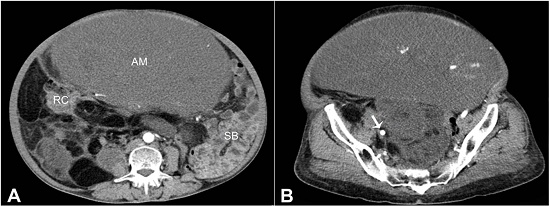

A 57-year-old female presented with an abdominal swelling over the last 6 months, and pain during the last 2 months. She also had a prolapsed uterus, which was diagnosed 3 months ago. She had no co-morbidities. A history of radiation exposure or any previous surgery was absent. On examination, a large abdominopelvic lump was palpable, measuring about 25 cm in diameter. The lower border of the mass could not be felt. Routine investigations were within normal limits. The contrast-enhanced computed tomography (CECT) of the abdomen and pelvis scan showed a large abdominopelvic mass with homogeneous density and enhancement, predominantly on the right side, displacing the small bowel and urinary bladder to the left. The abdominal and pelvic CECT scan showed a large abdominopelvic mass with homogeneous density and enhancement after contrast injection, predominantly on the right side, displacing the small bowel and the urinary bladder to the left. The CECT also showed multiple small lesions in the abdomen, with a large right iliac mass abutting the right iliac vessels (Figures 1A and 1B). There was no bowel or any other visceral infiltration. The imaging findings were consistent with the diagnosis of a retroperitoneal liposarcoma.

On exploratory laparotomy, there was minimal free fluid in the abdominal cavity. A multilobulated soft tissue tumor measuring approximately 20 × 15 cm was seen arising probably from the mesentery or from the bowel wall of the right colon. Another mass measuring 8 × 6 cm was seen in the right iliac fossa abutting the iliac vessels (Figure 2). Multiple nodules of up to 3 cm were seen in the entire abdomen, and they appeared to be attached to the colon.